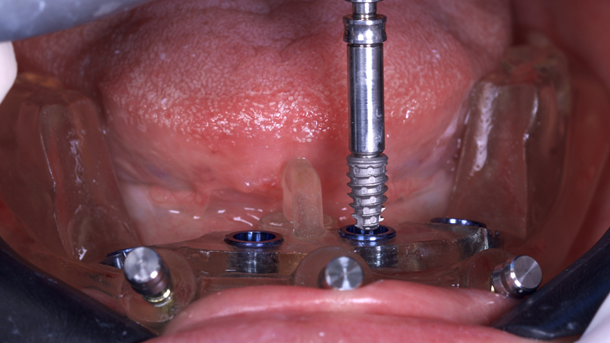

A cirurgia guiada para colocação dos implantes foi realizada em clínica odontológica sob anestesia local, Cloridrato de Mepivacaína 2% com adrenalina. Anteriormente, a guia era testada na boca para verificar o encaixe perfeito.

O guia foi fixado após estabilização em oclusão com a prótese superior. Após a retirada do guia de oclusão, foi fixada a guia de fresagem e instalação dos implantes, que foram instalados com torques superiores a 32N, o que permitiu a captura imediata da prótese provisória através do pilar de titânio e resina de fluxo.